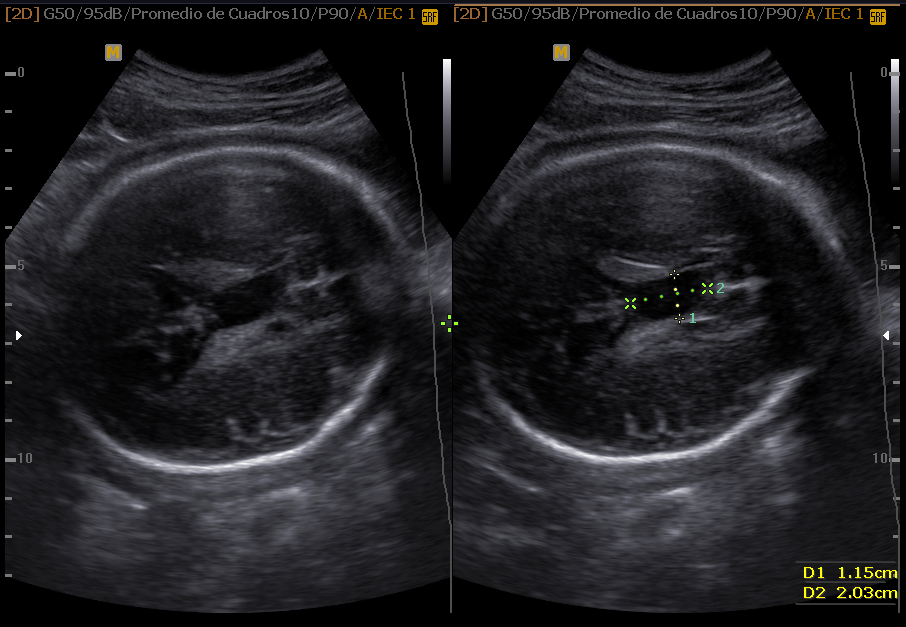

La Neurosonografía Fetal se refiere a la evaluación del Sistema Nervioso Central por Ultrasonidos: cráneo y su contenido (cerebro, ventrículos, tallo, cerebelo, etc.) y de la columna vertebral y su contenido (vértebras, médula espinal, líquido cefalorraquídeo, etc.).

Cráneo

Las estructuras intracraneales después de la semana 18-20 del embarazo son muy características y permanecen visualmente invariables hasta el final del embarazo, solo modificando sus tamaños a medida que el feto crece. Esto es de gran ayuda ya que permite determinar la aparición de cambios que podrían sugerir desviación de la normalidad y aparición de una malformación congénita o lesión adquirida por eventos externos especialmente relacionados a infecciones y accidentes vasculares fetales.